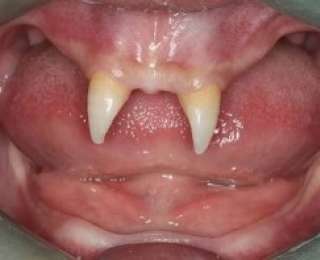

3. Подросток отрастил себе зубы вампира

У китайского мальчика выросло два очень острых передних зуба, в результате чего он стал похож на вампира. В декабре 2012-го года мать по имени Ван Хуэй отвезла своего сына Ван Пенфэя в местную больницу, на обследование. Мальчик из муниципалитета Чунцин после рождения очень плохо рос, а во рту у него появилось два острых клыка. Ван Хуэй пыталась выяснить причину появления во рту сына этих ненормальных образований, и посетила бесчисленное количество врачей, однако особого успеха это не принесло. Врачи из Юго-Западного госпиталя говорят, что её сыну можно будет сделать операцию, только когда он станет взрослым. Стоимость этой операции может варьироваться от 70000 до 80000 юаней, это примерно 15000 $. По словам Ван Хуэй, её сын становится всё более и более замкнутым, и часто дерётся с одноклассниками, которые шепчутся о нём, или косо смотрят на него.